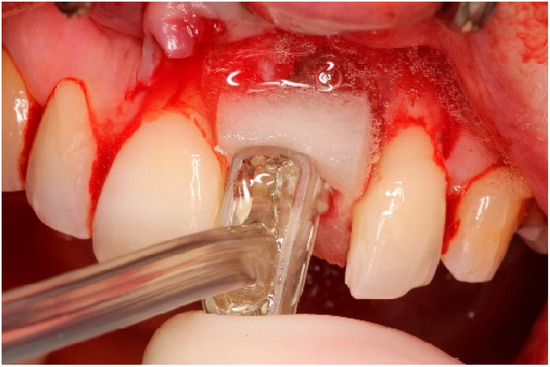

4. Timeline and Diagnostic Assessment

5. Therapeutic Intervention

5.2. Non-Surgical Pre-Treatment

5.3. Surgical Treatment